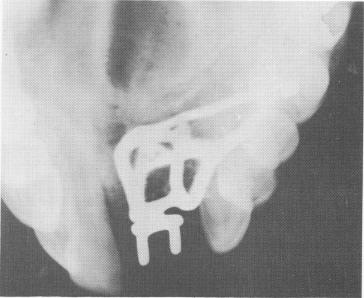

Fig. 12-97. A cross-sectional occlusal x-ray shows the subperiosteal implant with the horizontal transfixation pins.